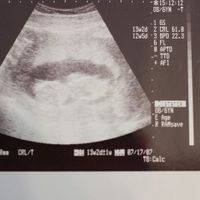

妊娠 11週~13週 で 胎児の頸部浮腫(NT)が有るか無いか Check。 胎児の後頸部に浮腫(頸部浮腫とかNTと呼びます)があると胎児に 染色体異常 や 内臓奇形(特に心臓奇形) が有る可能性があります。又 有るか無いかを調べる時期は妊娠11~13週です。超音波でダウン症かも診断されるケース こちらでは胎児のエコー写真を撮影した際、ダウン症が疑われる特徴を解説しています。 ただし個人差があるため、必ず胎児の段階で現れるとは限りません。 エコー検査ではっきりと判別できないことも少なくありません。 目次 クリックして表示 妊娠初期のエコー写真でダウン症が疑われる特徴 初期に後頭部・首のチャーミー小結さんの妊娠14週目のエコー写真 命の始まりは神秘的! 2D・3D・4Dのエコー写真で見る「私と赤ちゃんの実録260日」 なんと人の顔らしきものと背骨が見えます。 「ぽん太」という愛嬌あるネーミングにそぐわない端正な顔立ち・・・と早くも親バカを楽しみ始めた頃です。 つわりと一日中襲ってくる眠気との闘いを支えるモチベーションになってい

14週 エコー 異常- また、今回はエコー写真を載せますので、見たくな 13,14週のエコー写真 第二子は染色体異常でした ホーム ピグ アメブロ 妊娠14週から16週で ダウン症かどうかを調べる事は 出来るようですが、 100パーセントの確率では判明しません。 エコー検査で分かる症状は、 後頭部の浮腫等が見られるなど、 ダウン症の疑いがあるという範囲内にとどまります。

妊娠11週。 「まさか、と頭が真っ白になった」。 2週間後に絨毛(じゅうもう)検査を受け、赤ちゃんは ダウン症 と診断された。妊婦健診 14週2日 4dエコー ママと主婦の日々 妊婦健診 14週2日 4dエコー スポンサーリンク 3回目の妊婦健診。 今回から1ヶ月間隔の検診です。 赤ちゃんの4dエコーが見たいというパパのリクエストに応えて、パパと息子の3人で行ってきました。 エコーで性別がわかる? 妊娠14週の胎児は急速に成長するため、大きさには個人差がありますが、15週の終わり頃には身長約16cm、体重約100gになります(※1)。 平均より小さめでも、健診時に異常がなければ気にしないでくださいね。 妊娠14~15週までに

妊娠11週~14週 エコー超音波検査について 初妊娠10週目です。 昨日検診に行って次回は一ヵ月後でいいと言われました。 帰宅後パソコンなどで11週~14週はエコーで胎児の後頚浮腫などが発見しやすく染色体異常や心臓病などの可能性もわかるとありました。 頭大横径は261mm前後 妊娠14週に入ったばかりの赤ちゃんの頭大横径(BPD※)は、個人差はありますが、261mm前後*1となります。 ※妊娠中期以降になると、赤ちゃんは子宮内で手足を曲げているため、身長の推定は困難となります。 そこで、赤ちゃんの発育を確認する指標のひとつとして頭大横径(BPD:頭の最も大きい横幅)が用いられるようになります。 安定期といわれる妊娠5ヶ月に突入した16週目には胎児は約100gくらいになり、骨もしっかりして関節も完成し、背骨やあばら骨もエコーでみることができます。 耳もしっかり聞こえるようになるのでお母さんの声に反応することも。 また、脳の神経系が発達してくる時期で、自分の医師で手足を動かしたり、物事を記憶することもできるようになります。 出典

妊娠13週で異常が妊娠継続を決断し、悲しい別れをした夫婦の11年後 出生前診断と母たち(17)年月 河合 蘭 頭大横径は261mm前後 妊娠14週に入ったばかりの赤ちゃんの頭大横径(BPD※)は、個人差はありますが、261mm前後*1となります。 ※妊娠中期以降になると、赤ちゃんは子宮内で手足を曲げているため、身長の推定は困難となります。 そこで、赤ちゃんの発育を確認する指標のひとつとして頭大横径(BPD:頭の最も大きい横幅)が用いられるようになります。14週の時に胎児専門のドクターにエコーをして頂き、今の所、週数通りで問題はなさそうとの事でした。 染色体異常を調べる検査をするべきか相談したところ、しなくても大丈夫でしょ。 と言われ安心していました。 しかし、色々調べていると18